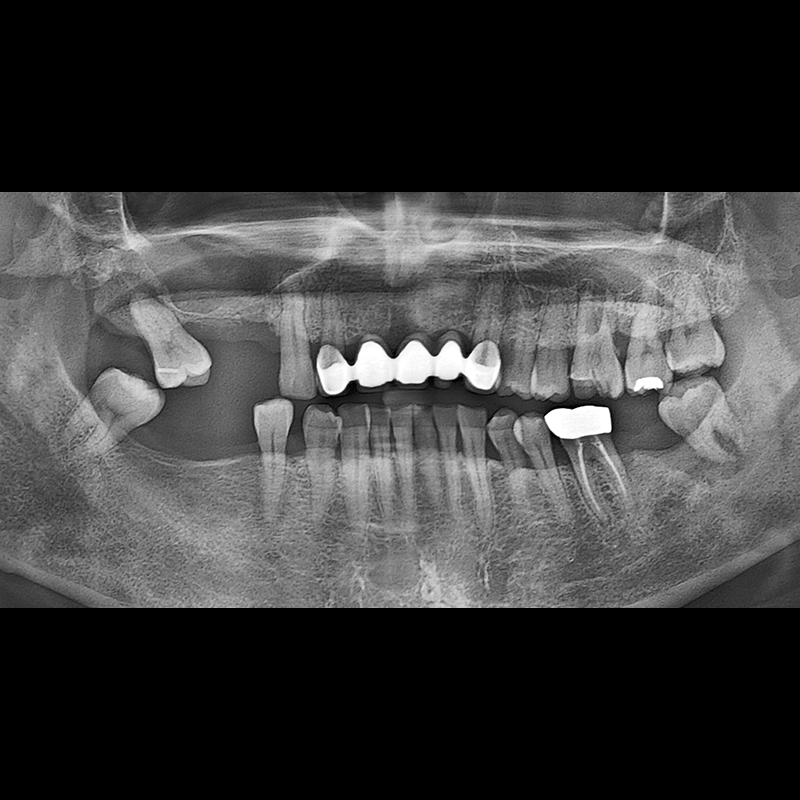

BEFORE AFTER

Implant before and after 2025.05.30

Implants were placed in the missing tooth and in the tooth position where it was difficult to save.